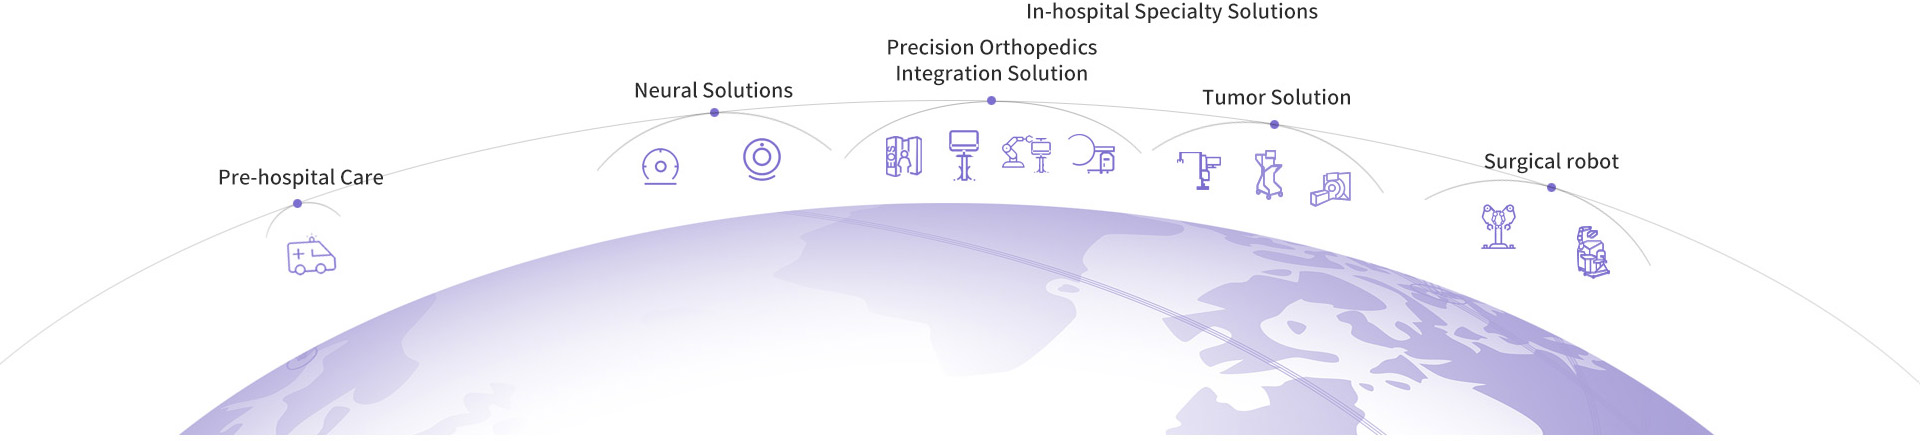

Solutions from Pre-hospital Emergency to In-hospital Specialty

In the field of professional medical technologies and products, clinical demands are based on to target the medical technology and service market by providing solutions which range from mobile pre-hospital care to professional in-hospital surgery and covers medical devices, high-end surgical robots and medical consumables for core fields such as pre-hospital emergency, neurosurgery, orthopedics, and oncology.